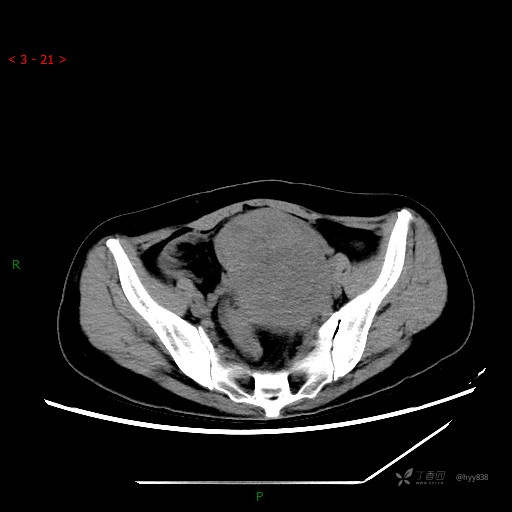

辅助检查:CT

增强动脉期